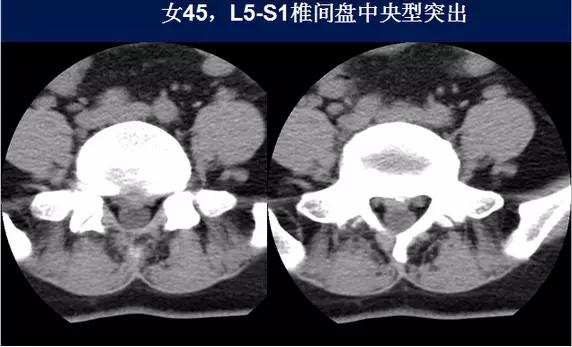

⑴中央型:椎间盘影局限性超出椎体边缘,硬膜囊可受压,硬膜外脂肪间隙变窄、消失,可伴纤维环钙化。

硬膜外脂肪间隙变窄、消失,可伴纤维环钙化。